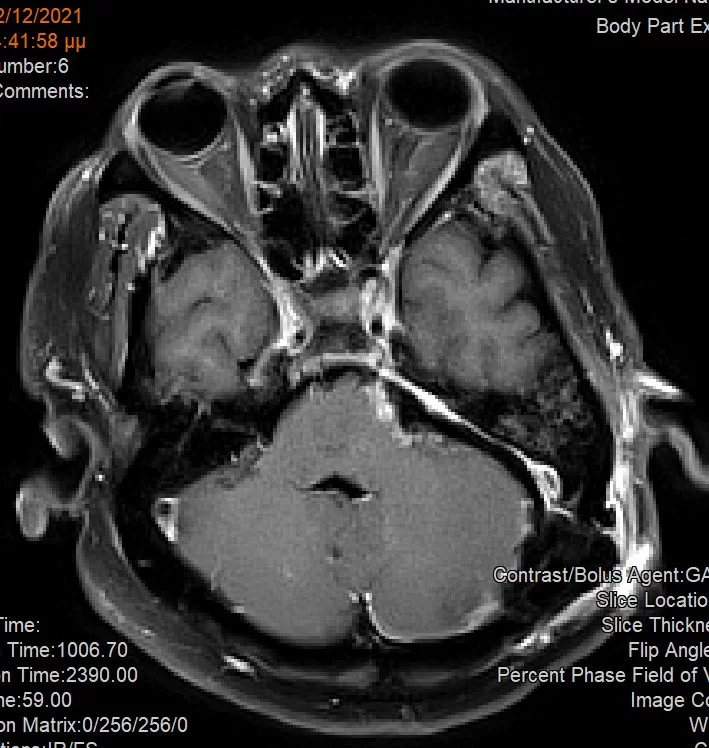

Η μετεγχειρητική μαγνητική τομογραφία εγκεφάλου (βλ. εικόνα) επιβεβαιώνει την πολύ καλή εξαίρεση του όγκου και την πλήρη αποσυμπίεση του εγκεφαλικού στελέχους.

Μετεγχειρητική Μαγνητική Τομογραφία Εγκεφάλου

Η μετεγχειρητική μαγνητική τομογραφία επιβεβαιώνει την αφαίρεση του όγκου και την αποσυμπίεση του στελέχους.